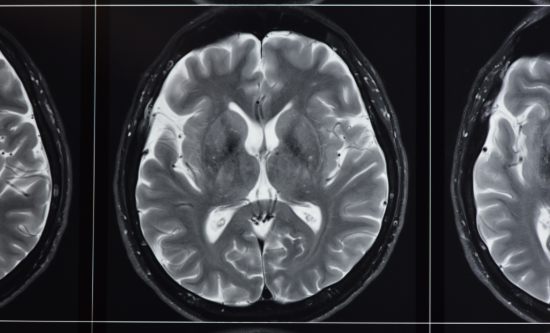

Image of an MRI scanned brain

University wins record funding for powerful UK MRI scanner

£29 million MRI scnanner ro help with clearer images for diseases treatment